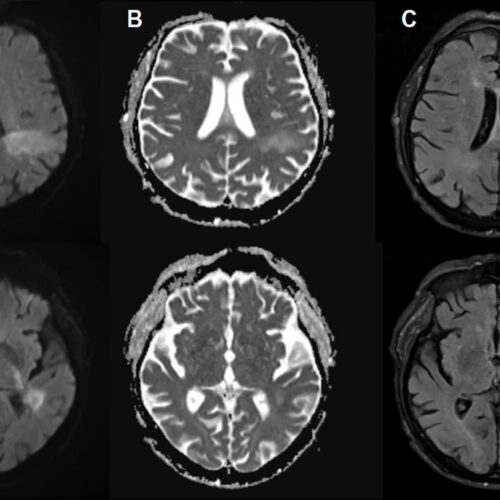

In PML, the new disease-causing virus or “PML-type” JC virus actively invades the brain, blowing up specific brain cells, including the cells that form the insulating myelin sheaths that protect nerve cells. This leads to extensive demyelination, which results in nerve cell dysfunction and death. On imaging, PML can show up as signature lesions in the brain. Those imaged lesions, paired with test findings of JC virus DNA in cerebrospinal fluid, are how PML is diagnosed. But for patients experiencing PML, the symptoms can mimic everything from a stroke to multiple sclerosis, causing problems like speech impairments, visual defects, motor dysfunction, and seizures.